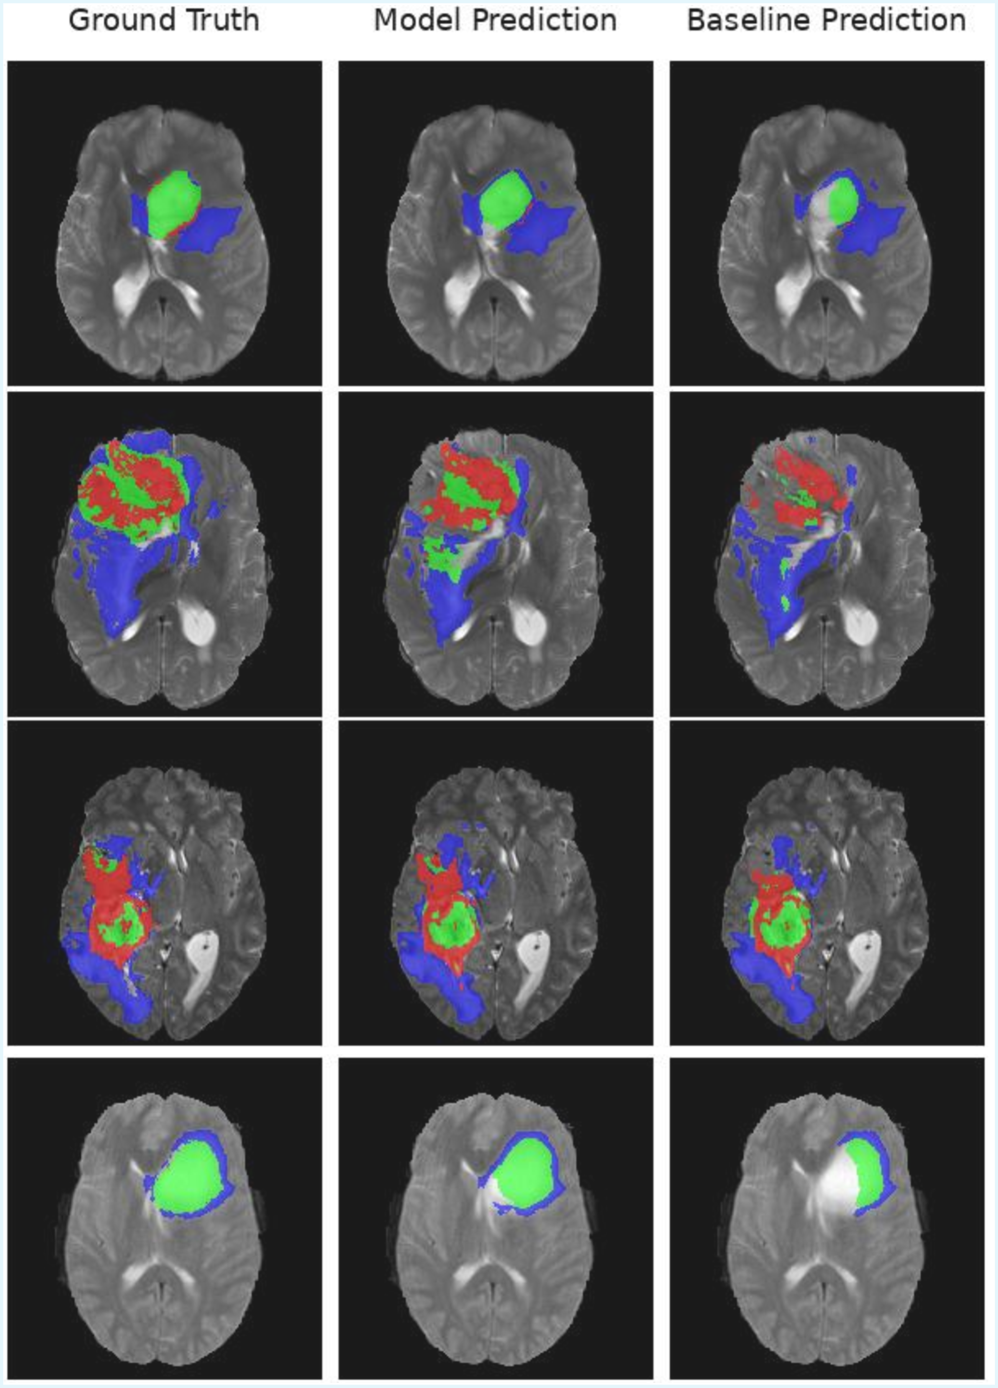

Refer to caption

Figure 2: Qualitative visualization of segmentation results on mmformer with BraTS18 dataset. Model Prediction is mmformer + fuzzy, Baseline Prediction is mmformer.

Full Modality Setting

Our method consistently enhances segmentation accuracy and reliability on the BraTS18 and Pretreat-MetsToBrain-Masks datasets. Under the full modality condition, where all four MRI sequences are utilized, results are presented with the mmFormer [48] and SwinUNETR [12] baselines in Table 1. These baselines, integrated with our strategy, show substantial improvements in mean Dice scores and consistent benefits across tumor subregions for both datasets. As illustrated in Fig. 2, the baseline models often struggle to delineate large, contiguous lesion areas, especially in regions far from the boundary. In contrast, our proposed method yields smoother and more complete spatial predictions. Baseline models frequently concentrate on high-uncertainty boundary regions, which can lead to overfitting due to ambiguous edge cues, resulting in fragmented and inconsistent segmentations. By incorporating a fuzzy auxiliary loss, our variant maintains coherent structures across the tumor core and enhancing tumor regions, effectively mitigating spurious uncertainty.